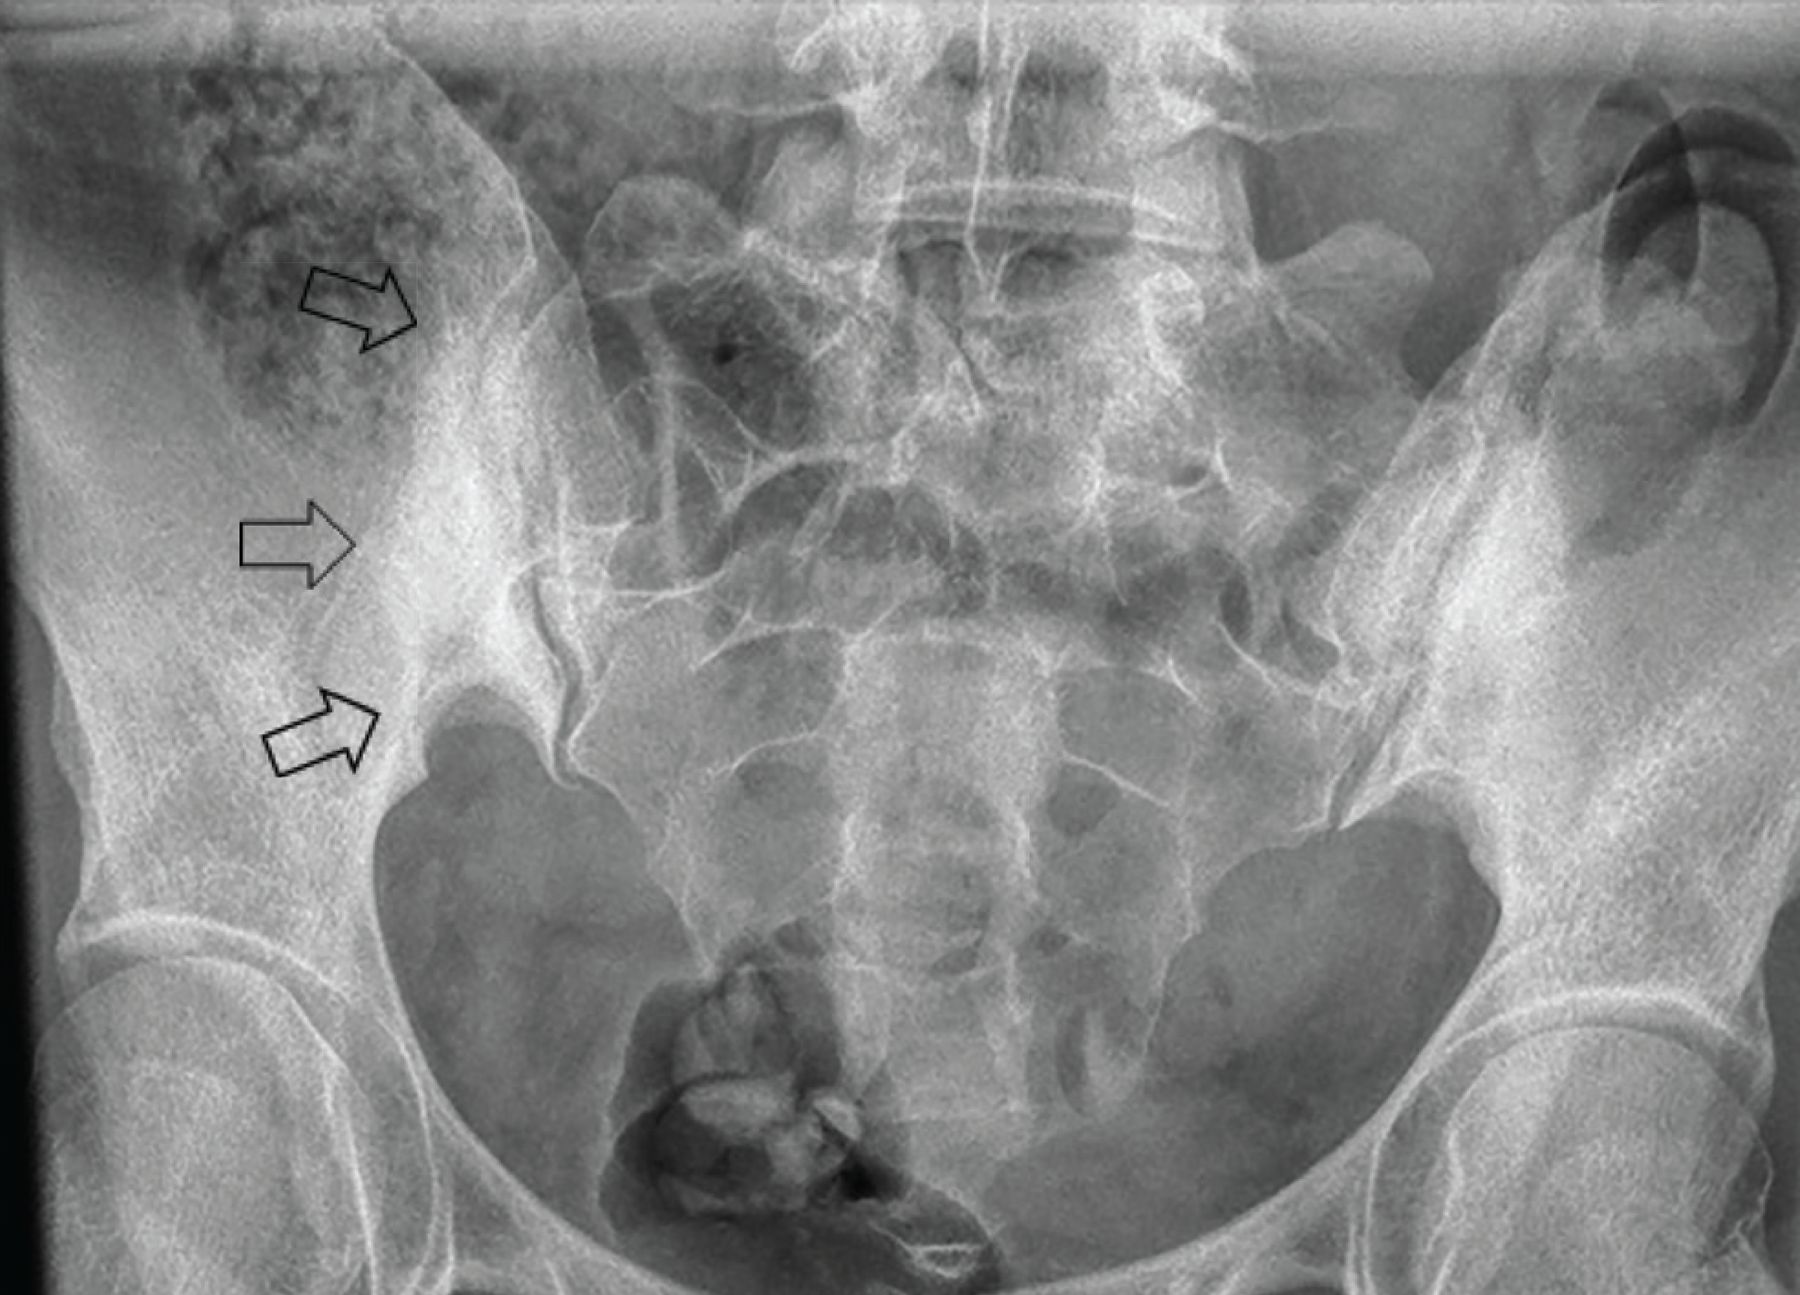

Plain radiography showed dense bilateral subchondral sclerosis on the iliac sides of the mid portion of the sacroiliac joints (Figure 2). These radiography findings and the earlier computed tomography findings were consistent with osteitis condensans ilii (OCI).

Radiograph of the sacroiliac joints from the patient’s evaluation at the rheumatology clinic shows bilateral subchondral sclerosis on the iliac side, consistent with osteitis condensans ilii. The triangular-shaped area of sclerosis, a hallmark radiographic feature of osteitis condensans ilii, is best appreciated on the right side (arrows).

Patients with OCI complain of intermittent axial low back pain with occasional hip area pain.2 This pain can be worse during the third trimester of pregnancy or post pregnancy. OCI can be an incidental radiographic finding in an asymptomatic patient. Radiographic findings of OCI include bilateral triangular (or oval) subchondral sclerosis predominant on the iliac side and the absence of erosions and ankylosis (Figure 2).3 Computed tomography may also show sacral subchondral sclerosis.